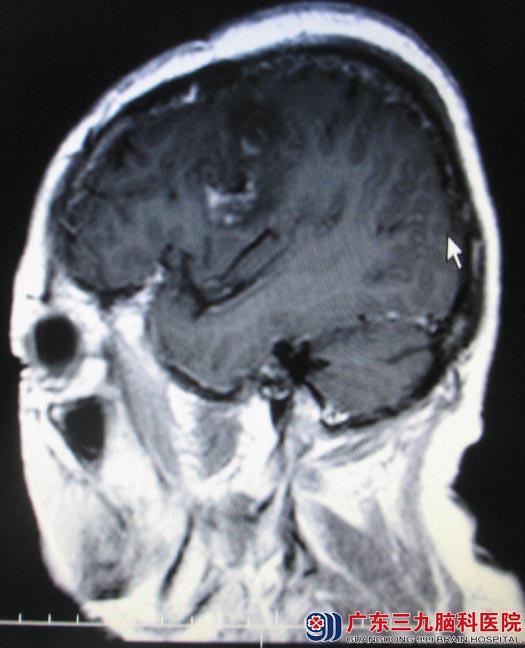

经过慎重的术前准备,5月26日由鲁明主任主刀,先作右侧顶部马蹄形切口,切开硬膜后见右侧顶部大脑镰窦旁灰白色肿瘤组织,肿瘤基底向矢状窦内生长,予显微镜下切开部分矢状窦,取瘤钳取出静脉窦内肿瘤,修补静脉窦,完全切除肿瘤。再作左额部弧形切口,在导航引导下皮层造瘘,见皮层下灰红色肿瘤组织,肿瘤呈鱼肉状,血供丰富,予显微镜下小心分离并切除。术后吴女士肢体运动等功能均恢复良好。病理回报:右侧顶部过渡型脑膜瘤(WHO1级);左侧额叶胶质肉瘤(WHOⅣ级)。